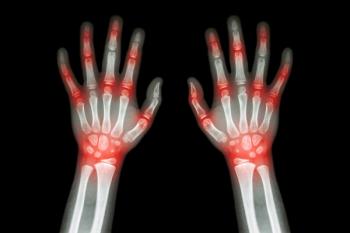

Weak handgrip strength may predict diabetes risk in postmenopausal women, highlighting the importance of muscle strength in diabetes prevention.